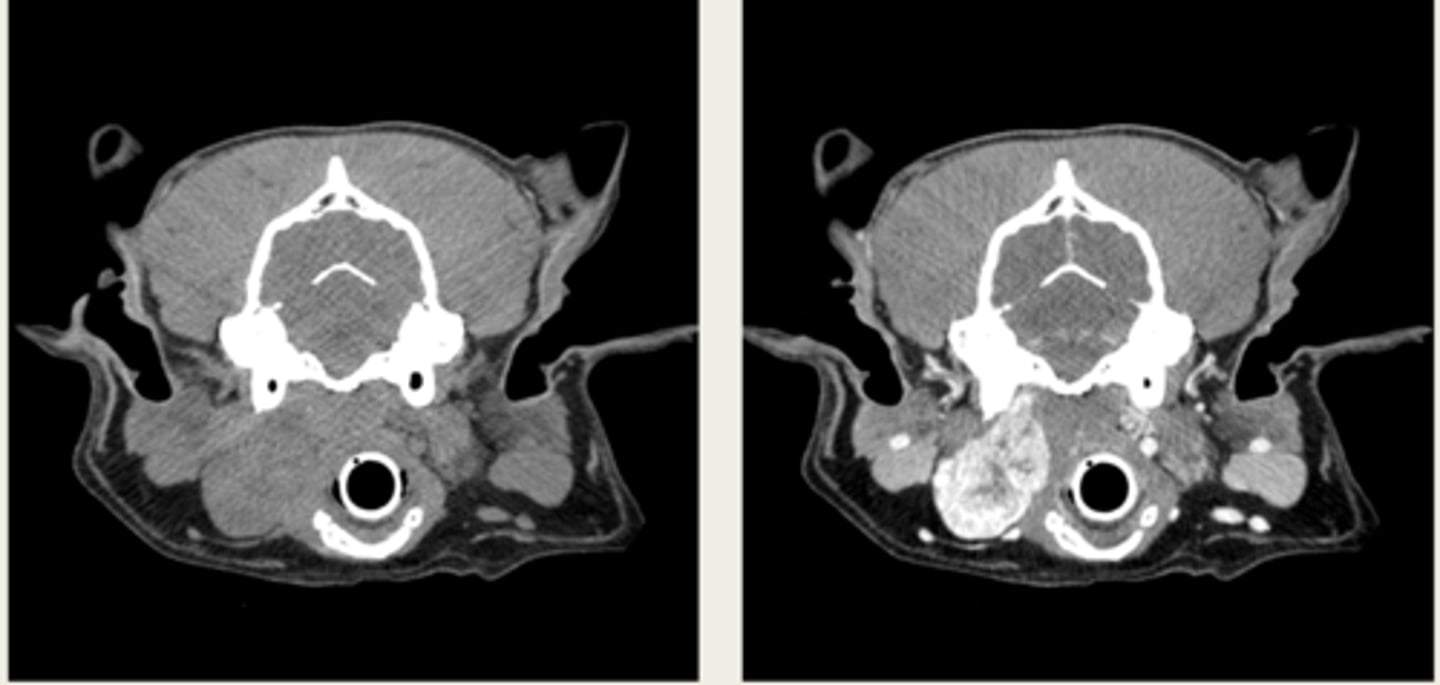

-cross sectional

-same area

-TRANSVERSE PLANE

how are these images the same?

right- bright bone

left- less bright bone, more definition in tissue

how are these images different?

left- MRI

right- CT

which one is the CT and which is the MRI?